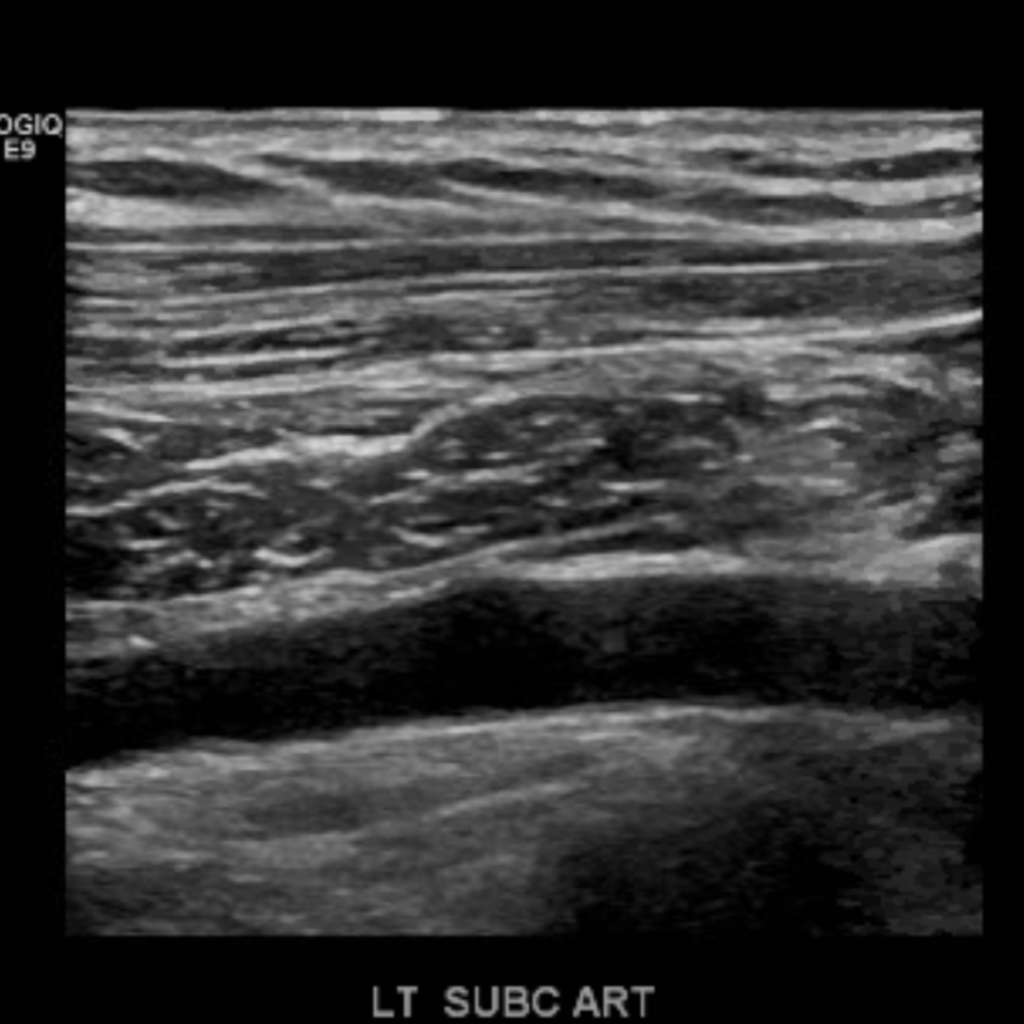

The subclavian artery arises from the brachiocephalic artery on the right and off of the aortic arch on the left. This artery further divides into the axillary, brachial, radial, ulnar, palmar and digital arteries respectively.